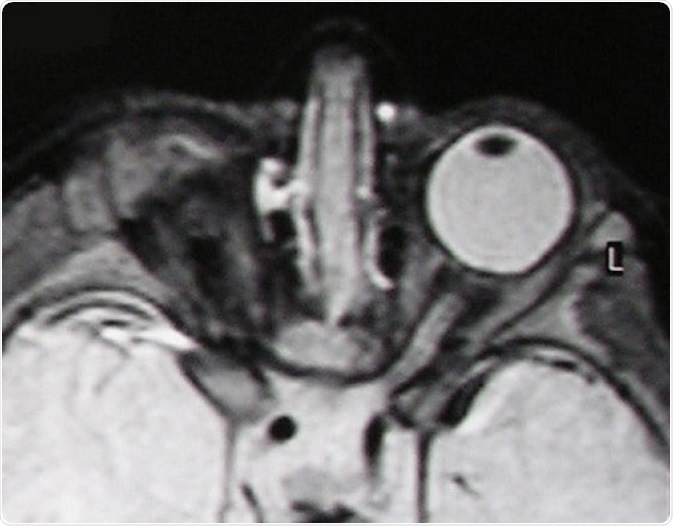

For example, some genetic mutations lead to anophthalmia (one or no eyes present) or microphthalmia (abnormally small eyes) whereas others lead to cell-specific defects like the absence of rods or cones at the back of the eye, the cells (photoreceptors) that are responsible for detecting light.

T2-weighted MR scan of a patient with unilateral anophthalmia. Note the presence of amorphous tissue and structures resembling extraocular muscles within the anophthalmic right orbit. The right optic nerve/chiasm junction appears attenuated rather than absent suggesting possible residual optic nerve neural tissue. © Verma AS / Wikimedia Commons.